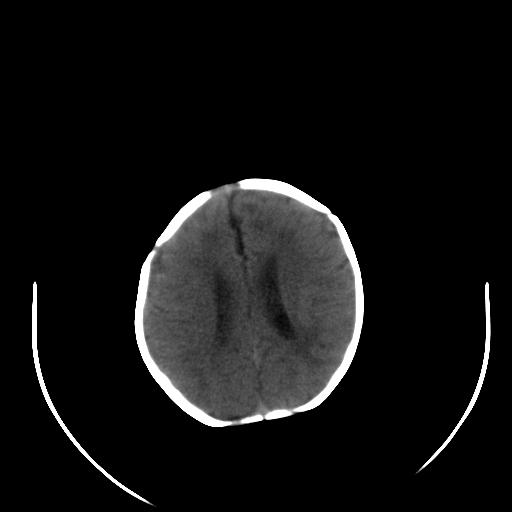

患儿 女性 1个月  今天发现阵发性抽搐  双眼上翻、凝视,嘴唇及面色青紫

考虑双侧脉络膜裂囊肿。

双侧颞枕叶片状低密度影,考虑新生儿却血缺氧性脑病可能

左侧额叶见班片样低密度灶,症状像癫痫,可能与之有关。

新生儿却血缺氧性脑病不排除!

左侧额叶见班片样低密度灶,建议mr

考虑hie。

考虑新生儿hie。